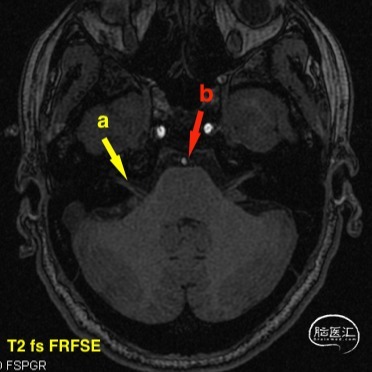

头颅MR(2021-07-23),面听神经复合体未见明显血管压迫。

a 黄色箭头为患侧面听神经复合体 b 红色箭头为动脉成像